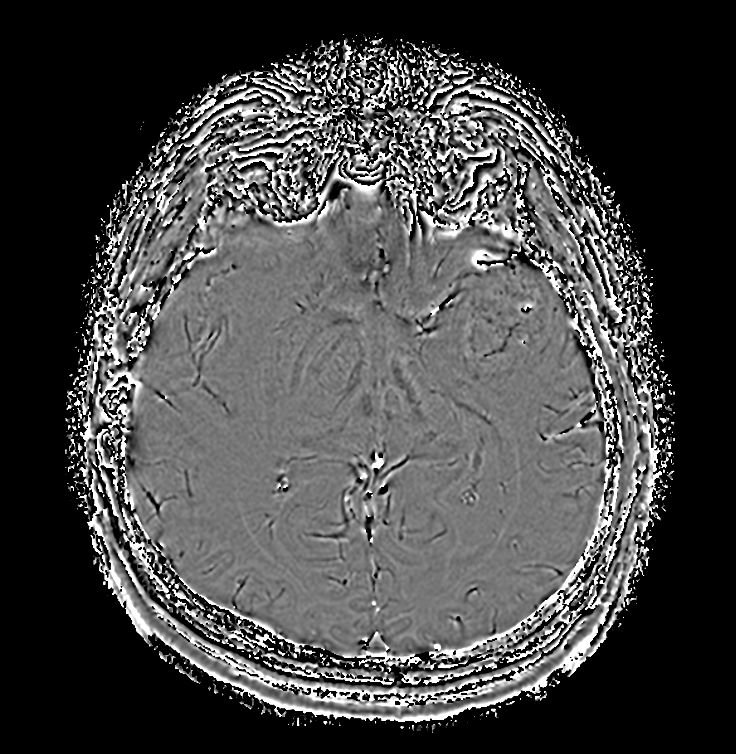

Axial SWIp (Phase)